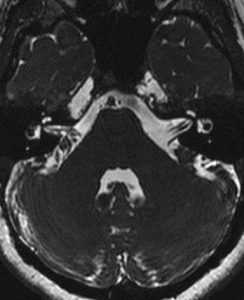

- Внутренний слуховой проход и мостомозжечковый угол - шваннома 8 нерва, менингиома височной кости, эпидермоидные (холестеатомы) и арахноидальные кисты, редко - гломусная тимпаническая опухоль.

Вестибулокохлеарный нерв (VIII) состоит из 4 пучков. Опухоли происходят обычно из вестибулярной его части. Шваннома - инкапсулированная доброкачественная (градация 1) опухоль, происходящая из дифференцированных неопластических шванновских клеток оболочек периферических нервов. Невриномы ММУ составляют около 3% опухолей головного мозга. Часть шванном (двухсторонние слуховых нервов) связана с НФ 2 типа. Пик частоты между 40 и 60 годами. Растут медленно и крайне редко малигнизируются. Клинические проявления связаны с нарушением функции нерва и компрессией ствола. Шваннома может происходить из любого отрезка по ходу нерва и хорошо прослеживается при МРТ области ММУ. Невринома видна как на Т2-взвешенных, так и на Т1-взвешенных МРТ в виде округлого образования. Невриномы хорошо и равномерно усиливаются после МРТ с введением контрастного вещества. Невриномы области цистерны могут иметь компонент во внутреннем слуховом проходе, особенно, хорошо видимый при МРТ головного мозга с контрастированием. Изредка встречаются невриномы полностью расположенные внутри канальца. Они составляют наибольшую диагностическую сложность при МРТ, требуют тонких срезов и контрастирования. Менингиомы ММУ обычно типично расположены и при МРТ имеют характерную форму и типичные черты при МРТ с контрастированием. Однако редко встречаются внутриканальцевые менингиомы. При МРТ они неотличимы от неврином. Холестеатомы при МРТ имеют смешанную интенсивность сигнала, в зависимости от их содержимого. На диффузионно-взвешенных МРТ холестеатомы обычно яркие.

МРТ головного мозга. Аксиальная Т2-взвешенная МРТ. Фрагмент ММУ. Холестеатома слева.

МРТ головного мозга наиболее информативна в плане выявления опухолей мостомозжечкового угла и кист этой области. Некоторое патологии, такие как расширение водопровода и лабиринтит также хорошо видны при МРТ. КТ лучше демонстрирует состояние внутреннего уха.